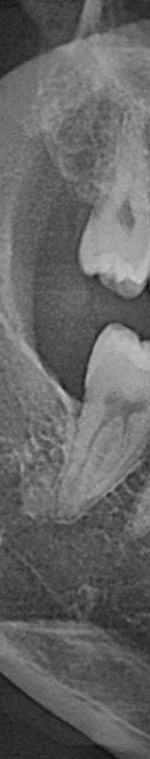

턱 뼈와 치아 사이에 공간이 충분하지 않기 때문에 누워서 올라오거나 매복되어 자라는 경우가 많았어요. 반포치과를 찾는 분들의 사랑니의 경우 매복된 경우도 많고 이가 완전히 잇몸 밖으로 나오지 않아서 일반 치과에서는 발치가 어려웠어요. 사랑니발치가 왜 필요한지 가끔 의문을 가지는 분이 계셨어요. 사랑니발치를 왜 해야 하는지 알려드리겠어요. 사랑니는 다른 치아처럼 바르게 나는 경우도 드물게 있긴 하지만 대부분 어금니 쪽으로 기울어져서 올라오거나, 완전히 수평으로 누워서 자라는 경우도 있었어요. 누워서 자라는 치아는 옆의 치아를 밀어 치열이 비뚤어지고 부정교합을 유발했어요.

사랑니가 90도로 누워서 난 경우는 수평 매복, 뼈나 잇몸에 사랑니가 완전히 덮여서 아예 보이지 않는 경우는 완전 매복, 일부분만 잇몸이나 뼈에 덮여있는 경우 부분매복이라고 했어요. 대부분의 환자분이 이런 매복 중에 한 가지에 해당하기 때문에 시술이 매우 어려웠어요. 특히 사랑니 주변으로는 구강과 관련된 중요한 신경 조직이 인접하여 있기 때문에 고난이도 시술이라고 할 수 있었어요.

사랑니발치를 하기 위해서는 먼저 파노라마 x선 사진을 통해 발치 시 신경에 영향을 줄 수 있는지 확인하는 과정을 진행했어요. 이 과정을 통해서 충분히 의사와 상담을 한 후 처방전을 발급했어요. 이 때 처방전에는 항생제를 포함하여 발치 후 통증을 대비한 진통제를 처방했어요. 환자에게 충분히 설명한 후에 국소마취를 진행하고 마취가 된 다음에 절개를 최대한 덜 하는 방향으로 수술하여 사랑니를 발치했어요.